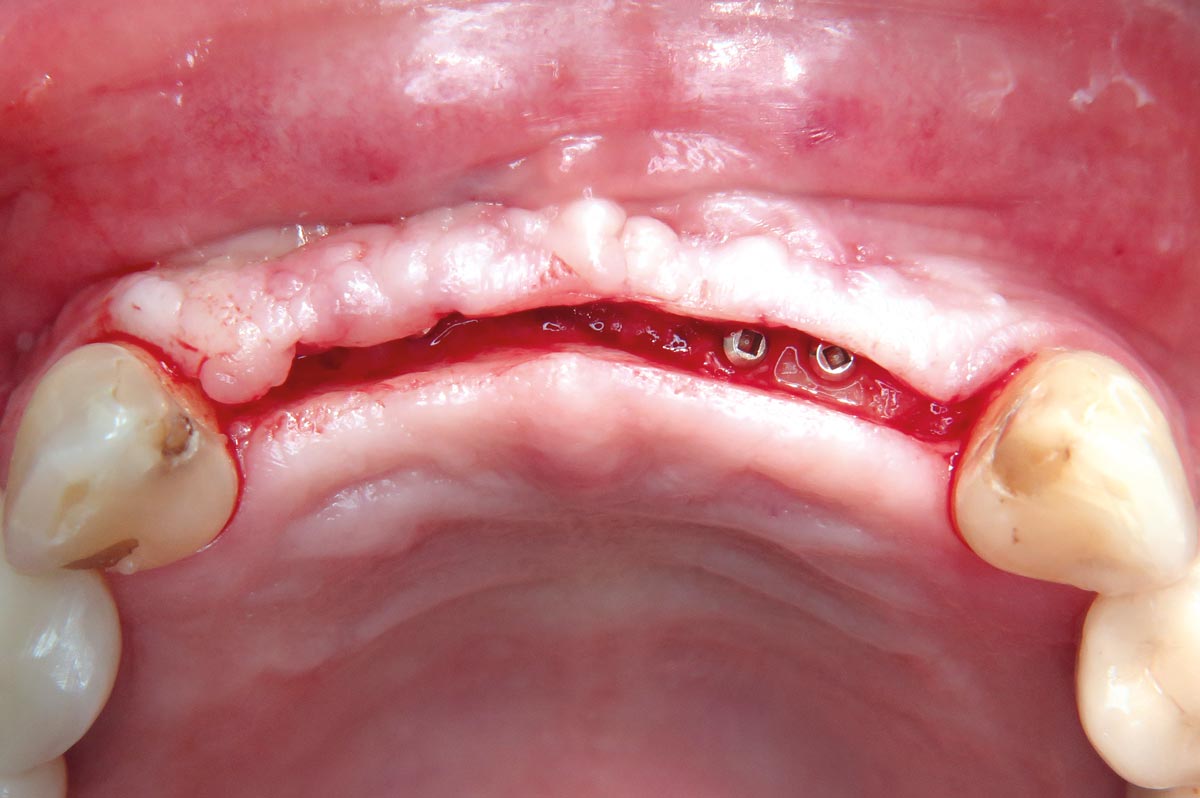

02 / 22 - Flap projection and demonstration of bone defect

Three-dimensional augmentation with maxgraft® cortico - M.Sc. E. Kapogianni